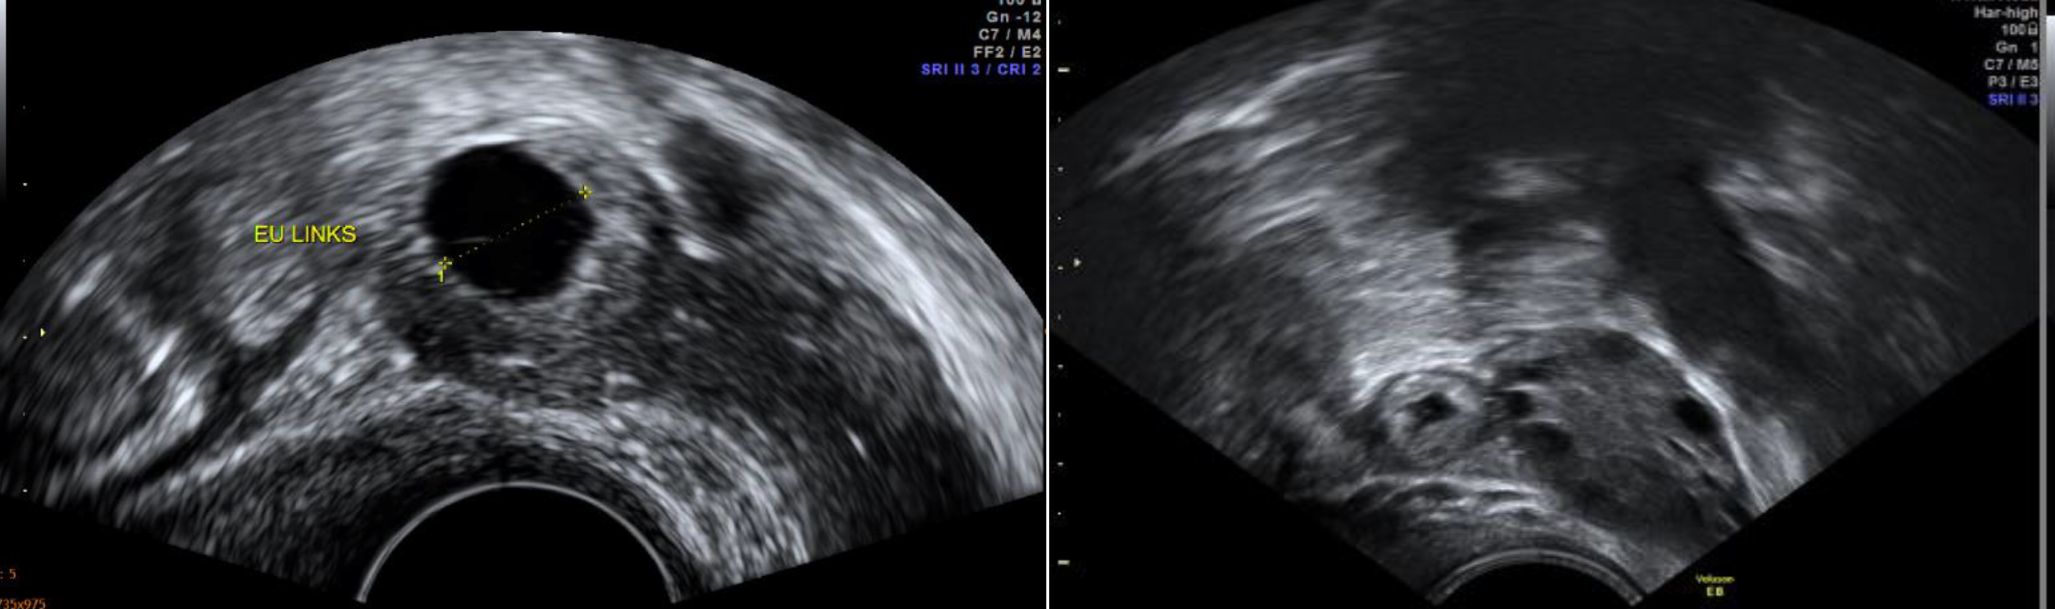

Abb. 1

Transvaginal-sonographische Darstellungen von ektopen Graviditäten mit „bagel sign“

Der sonographische Nachweis einer ektopen Chorionhöhle mit Dottersack und Embryonalstruktur gelingt selten, häufiger lassen sich inhomogene Raumforderungen im Adnexbereich („blob sign“) oder ein Gestationssack innerhalb dieser Raumforderungen („bagel sign“, siehe Abb. 1) darstellen. Zusätzlich kann eine Flüssigkeitsansammlung im Cavum uteri im Sinne eines Pseudogestationssacks auffallen.